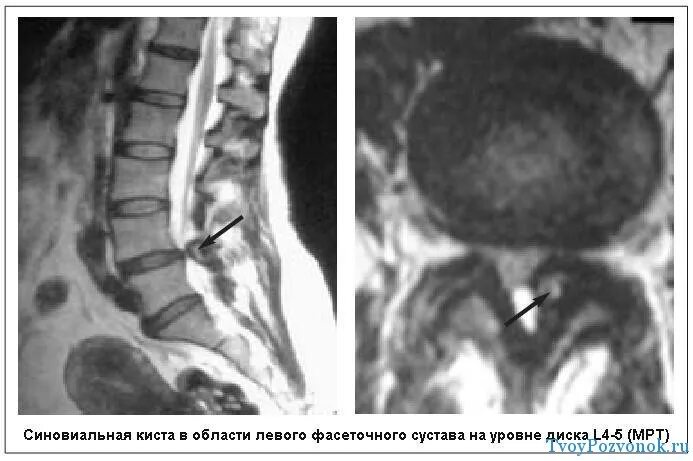

Киста в грудном отделе позвоночника